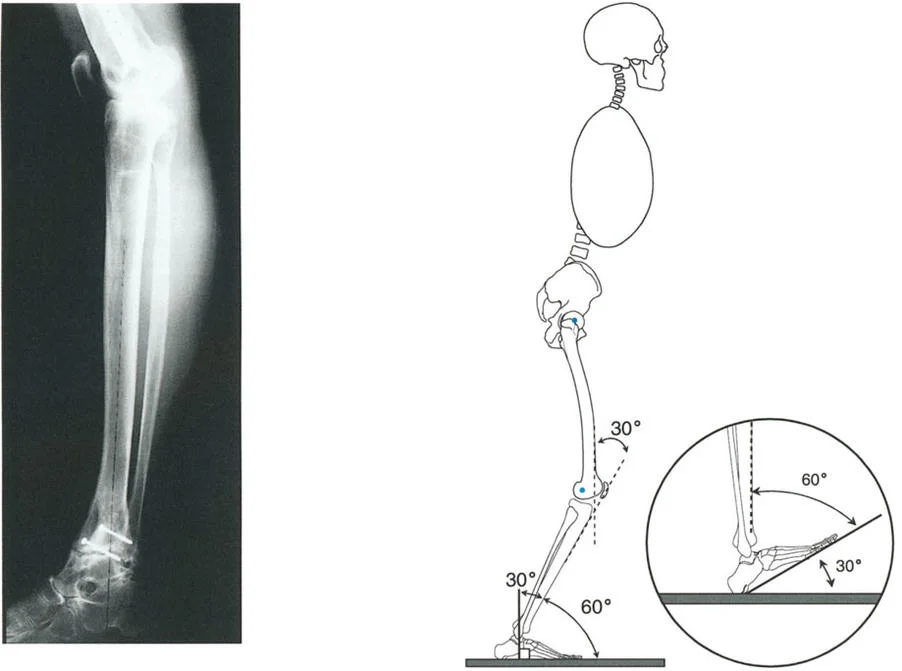

* الأشعة السينية (X-rays) الواقفة لكامل الطرف السفلي: هذه الأشعة ضرورية لتقييم المحاذاة الكلية للطرف السفلي تحت تأثير وزن الجسم. يطلب الأستاذ الدكتور محمد هطيف صورًا شعاعية كاملة الطول للساق أثناء الوقوف (Full-length standing alignment films) لتقييم المحور الميكانيكي للساق وتحديد زوايا المفاصل بدقة.

قوة رد الفعل الأرضي وميكانيكا الكاحل

عند الوقوف على ساق واحدة، تنشأ قوة من الأرض (تُسمى قوة رد الفعل الأرضي) وتمر عبر الطرف السفلي. هذه القوة تقع بشكل طبيعي على الجانب الخارجي للقدم وأمام مركز دوران مفصل الكاحل. هذا التوضع يؤدي إلى:

* عزم تقوس وحشي (Valgus Moment): يدفع الكاحل والقدم إلى الخارج.

* عزم انثناء ظهري (Dorsiflexion Moment): يدفع القدم إلى الأعلى.

لمواجهة هذه القوى الطبيعية والحفاظ على استقرار الكاحل، يجب أن تعمل عضلات معينة في الساق والقدم بجد. على سبيل المثال، تعمل عضلة الظنبوب الخلفية (Tibialis Posterior) وعضلات الساق الخلفية (Gastro-soleus complex) باستمرار للحفاظ على القدم مستقيمة ومسطحة على الأرض.